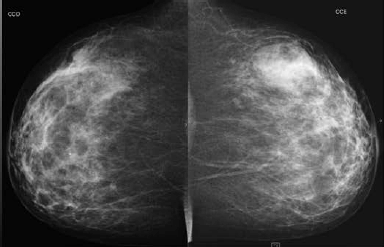

Paciente de 40 anos realizou esta mamografia para rastreio, sendo assintomática. A ultrassonografia realizada em outro serviço, 6 meses antes da mamografia, demonstrou pequeno nódulo hipoecoico de 1,5 cm no QSE da mama direita e nenhuma lesão na mama esquerda. Assinale a alternativa correspondente à hipótese diagnóstica da imagem nodular da mama esquerda observada na mamografia.